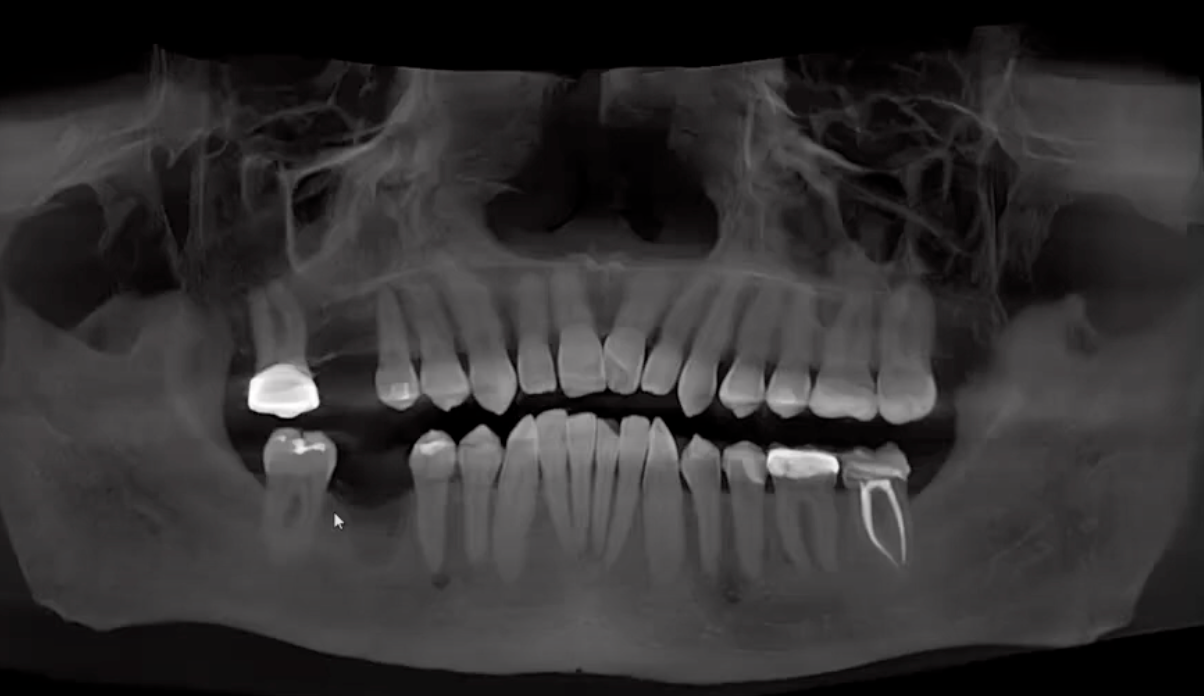

"Now, this patient was referred for removal of fractured teeth #4 and #5 with grafting. Once the patient had healed, we brought the patient back. We got the CEREC scans and we got the cone beam. So let's see how we plan a ghost implant. So the first thing that you do here is you align the crosshairs up right over tooth #3, where the implant had been placed about 10 years ago. And really once that's all set, the next thing that you're going to do is go ahead and set up and place the ghost implant.

"Now why is it a ghost implant? Because I'm putting it directly and perfectly over #3 because I'm going to use this ghost implant on #3 to parallel the implant for #5 so we can have a screw-retained bridge. So once you've got that ghost implant placed, you go ahead and bring the SSI file in like we normally do to bring in the crown proposal for tooth #5.

"Once that's in, you go ahead and you select Implant for #5, and make sure to click Parallel to #3 so it'll make that parallel for the bridge. And once you've done that, you go ahead and bring that virtual implant in for #3, parallel #3 for #5. So once that's done, you go ahead and choose your sleeve and make sure your spacing is correct to do the 360° turn. And then we go ahead.